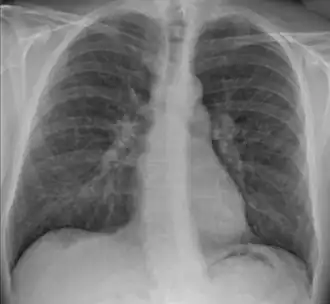

- radiologiques, presque constamment présents[37], où on distingue quatre stades :

- stade 1 : adénopathies médiastinales bilatérales et symétriques,

- stade 2 : adénopathies médiastinales et infiltrat/micronodules interstitiels,

- stade 3 : infiltrat/micronodules interstitiels sans adénopathies médiastinales,

- stade 4 : fibrose ;